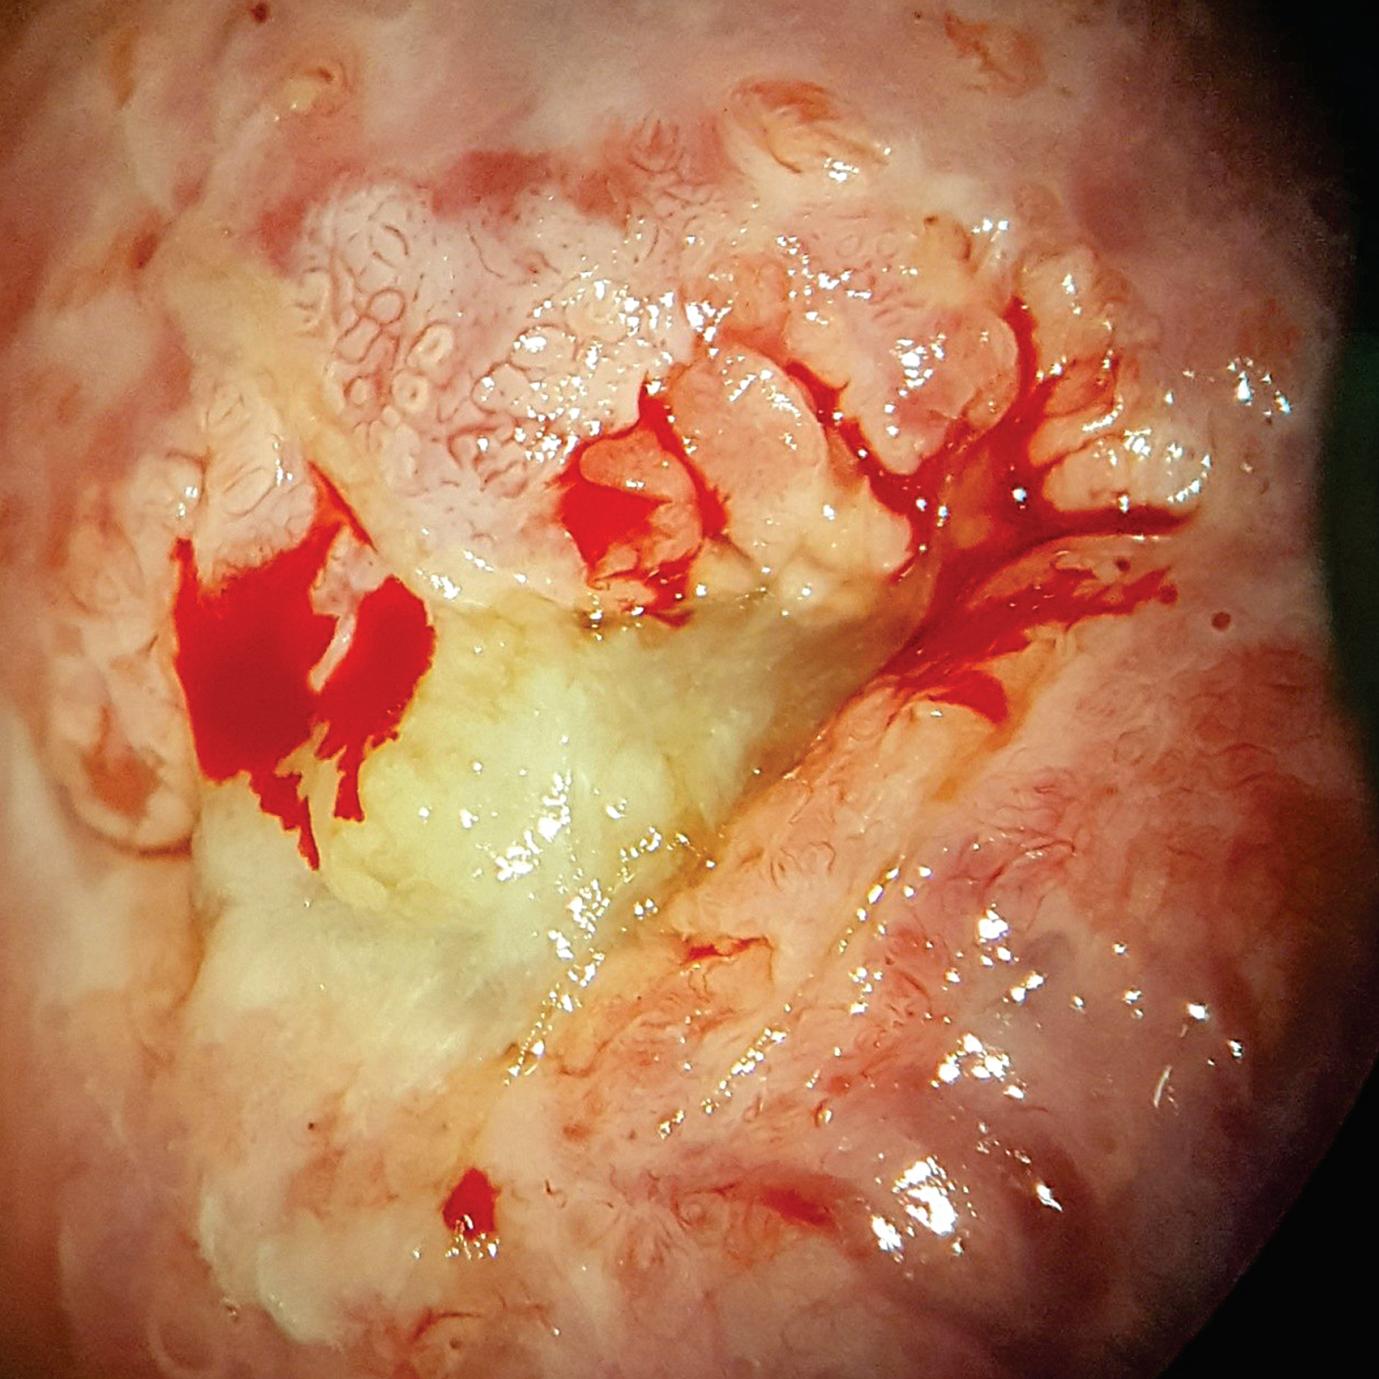

O diagnóstico correto da ectopia é feito por meio do exame colposcópico após a aplicação do ácido acético que tornará a junção escamocolunar mais evidenciada pela presença de um bordelete esbranquiçado. Muitas vezes o fenômeno ectópico é erroneamente diagnosticado levando a tratamentos desnecessários (Figs. 2-18 e 2-19).

que deverá ser aplicado profundamente na vagina em noites alternadas no total de 15 aplicações. O creme vaginal de clostebol também poderá ser utilizado da mesma maneira. Se a queixa permanecer e não ocorrer a epidermização da área, poderá ser realizado ambulatorialmente a aplicação de ATA a 80% sobre a área da ectopia. A aplicação deverá ser antecedida pela colocação de um chumaço de algodão no fundo vaginal que funcionará como protetor, pois o ácido em contato com a mucosa vaginal poderá causar ulcerações na mesma. O cotonete deverá ser pressionado levemente contra o colo até o aparecimento de uma coloração branca no local. As aplicações do produto deverão ser realizadas semanalmente durante em média 3 semanas. Em caso do aparecimento de efeitos colaterais como candidíase vaginal, as aplicações poderão ser feitas quinzenalmente (Fig. 2-20).

do colo uterino. A grande vantagem do ATA é que o mesmo propicia uma cauterização da superfície epitelial sendo que o mesmo não atinge o tecido conjuntivo protegendo então o colo de uma possível esclerose.